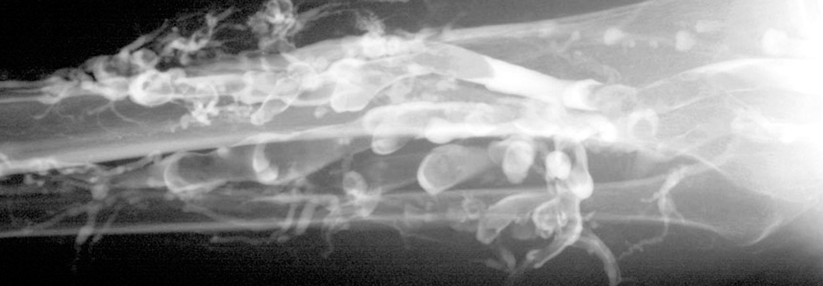

Lungenembolie mit Nachweis eines großen Thrombus innerhalb der rechten Pulmonalarterie. Lungenembolie mit Nachweis eines großen Thrombus innerhalb der rechten Pulmonalarterie. © wikipedia/Bernd Brägelmann Braegel (CC BY-SA 3.0)